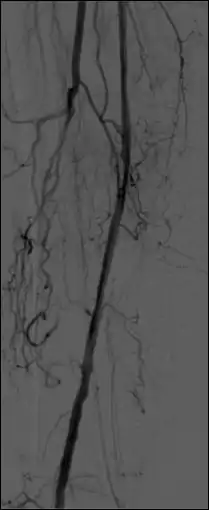

- The temporal-averaging feature of digital noise reduction can also be used for image presentation purposes so that the time course of the movement of contrast medium during a study can be displayed using just one image - see an example in Figure 7.4 from the peripheral study shown above - instead of a sequence of numerous images. Such an image is sometimes referred to as a Vascular Trace.

- One method of temporal filtration, referred to as Integrated Mask-Mode DSA involves adding (also called integrating) a number of images, acquired prior to the arrival of the contrast medium, to form an integrated mask image and adding a number of peak-opacification images to form an integrated live image. This is the process that was used to generate the vascular trace image in Figure 7.4. Thus, when four images are used to generate each integrated mask and live images, eight of the 25 images are now used in the subtraction process and, as a result, only 68% of the dose is wasted, and a subtraction image with lower noise results.

- Additional processes involve Bolus Chasing, Rotational Angiography and Volume Tomographic Angiography. Bolus Chasing[28] has been found to be particularly helpful in peripheral angiography, for example. Here, the progress of the contrast medium is tracked automatically and used to increment the table and/or XRT/image receptor movement to the next anatomical region. The subsequent set of subtraction images can then be used to construct a composite image of the peripheral vasculature. In Rotational Angiography[29], a C-arm assembly, for example, can be caused to rotate at 10 - 30 degrees per second during the imaging sequence. Subsequent dynamic display of the subtraction images can be used to generate a perceived 3D presentation so that complex relationships within the vasculature can be more readily appreciated. Volume Tomographic Angiography[30] is similar to Computed Tomography (CT) where the C-arm is rotated around the patient during the imaging sequence. The image data is subject to a volume reconstruction algorithm which permits generation of three-dimensional images of the opacified vasculature. We will consider this latter process in more detail below.